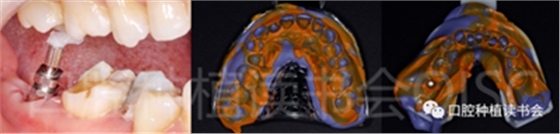

5.1 術前情況:

患者為70歲女性,右下后牙樁核冠因遠中牙根縱裂脫落,全身健康狀況良好,輕度骨質(zhì)疏松??趦?nèi)檢查:47殘根,遠中根縱裂,部分根面已腐至齦下2mm,叩(++),松(-);48近中傾斜阻生,咬合關系、修復間隙及牙周情況正常(圖12)。

圖12 遠中根縱裂及根面齲導致47殘根無法保留。

術前CBCT(美亞光電)檢查:47根分叉下方骨高度及骨寬度滿足即刻種植要求(圖13)。

圖13 47根分叉區(qū)骨寬度及骨高度(與下頜神經(jīng)管之間的距離)滿足即刻種植要求。